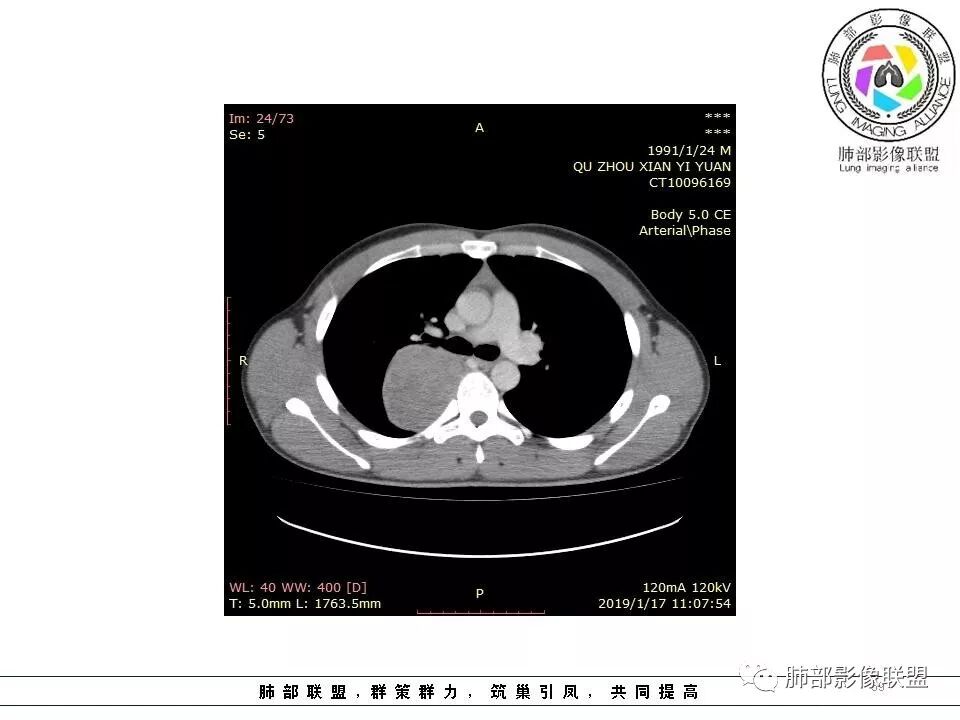

青年男性,间断胸痛;右侧脊柱旁可见一类圆形软组织密度影,密度欠均匀,增强扫描呈轻中度持续强化,邻近肺组织及肺动脉推移,可见肋间动脉供血,部分胸膜下脂肪可见,部分层面似见与右侧椎间孔相连。考虑后纵隔神经源性肿瘤。

右肺占位,跨越上叶后段、下叶背,边缘光滑,瘤肺界面清,见肺压缩缘(线样不张`强化),见胸膜尾征,胸膜下脂肪未见明显增厚,肋骨丶脊柱未见侵袭及受压,渐进性丶地图样强化,冠状位似见体循环供血

诊断:SFT(来源壁层胸膜?一般小于20%)

鉴别:神经源性(鞘瘤)、LCD、肉瘤丶孤立性间皮瘤

3.相邻椎间孔未见扩大,也未见块影延入椎管,易起自于神经根的鞘瘤似乎找不到支持点。

可惜未提供矢状位骨窗图像,如在肋骨内下缘观察到压迹有助于肋间神经的鞘瘤的判断,这是因为二者之间密切的毗邻关系。

4.静脉期轻度不均匀强化,注意不是环形强化,亦未见明确的“AB区”,这点也不支持神经鞘瘤。临床及病灶轻度强化都不支持副节瘤。

尽管神经纤维瘤的诊断确实有些出乎意外,但病例开阔了我们的视野。

未见多发病灶,患者有无脑内及皮肤病变,资料未能提供,稍显遗憾。